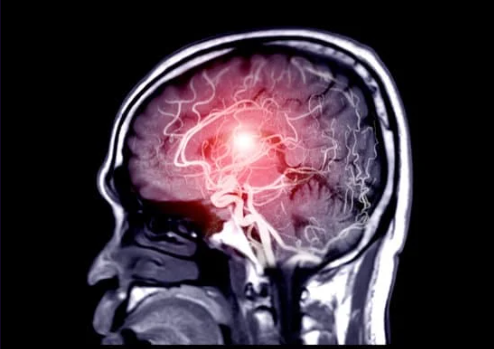

초기 알츠하이머는 신경과 전문의와의 상담을 통해 진단할 수 있으며, 인지 검사와 함께 MRI 또는 CT 스캔을 통해 뇌 구조를 확인하는 과정이 포함됩니다. 이러한 진단 도구들은 뇌의 변화 상태를 파악하는 데 중요한 역할을 하며, 조기 진단이 가능하도록 돕습니다.Q: 알츠하이머 초기 증상과 치매의 차이는 무엇인가요?